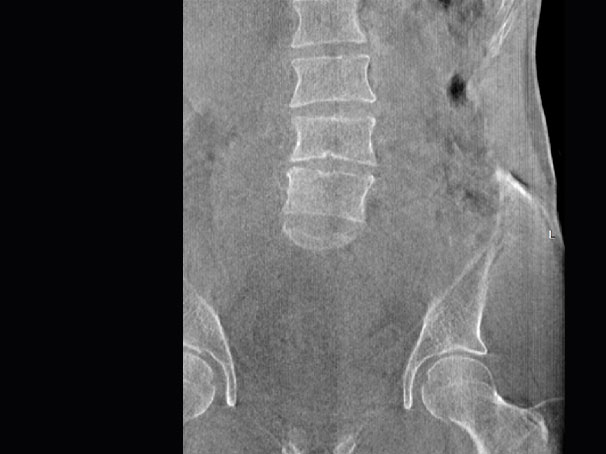

关闭金属伪影校正

开启金属伪影校正